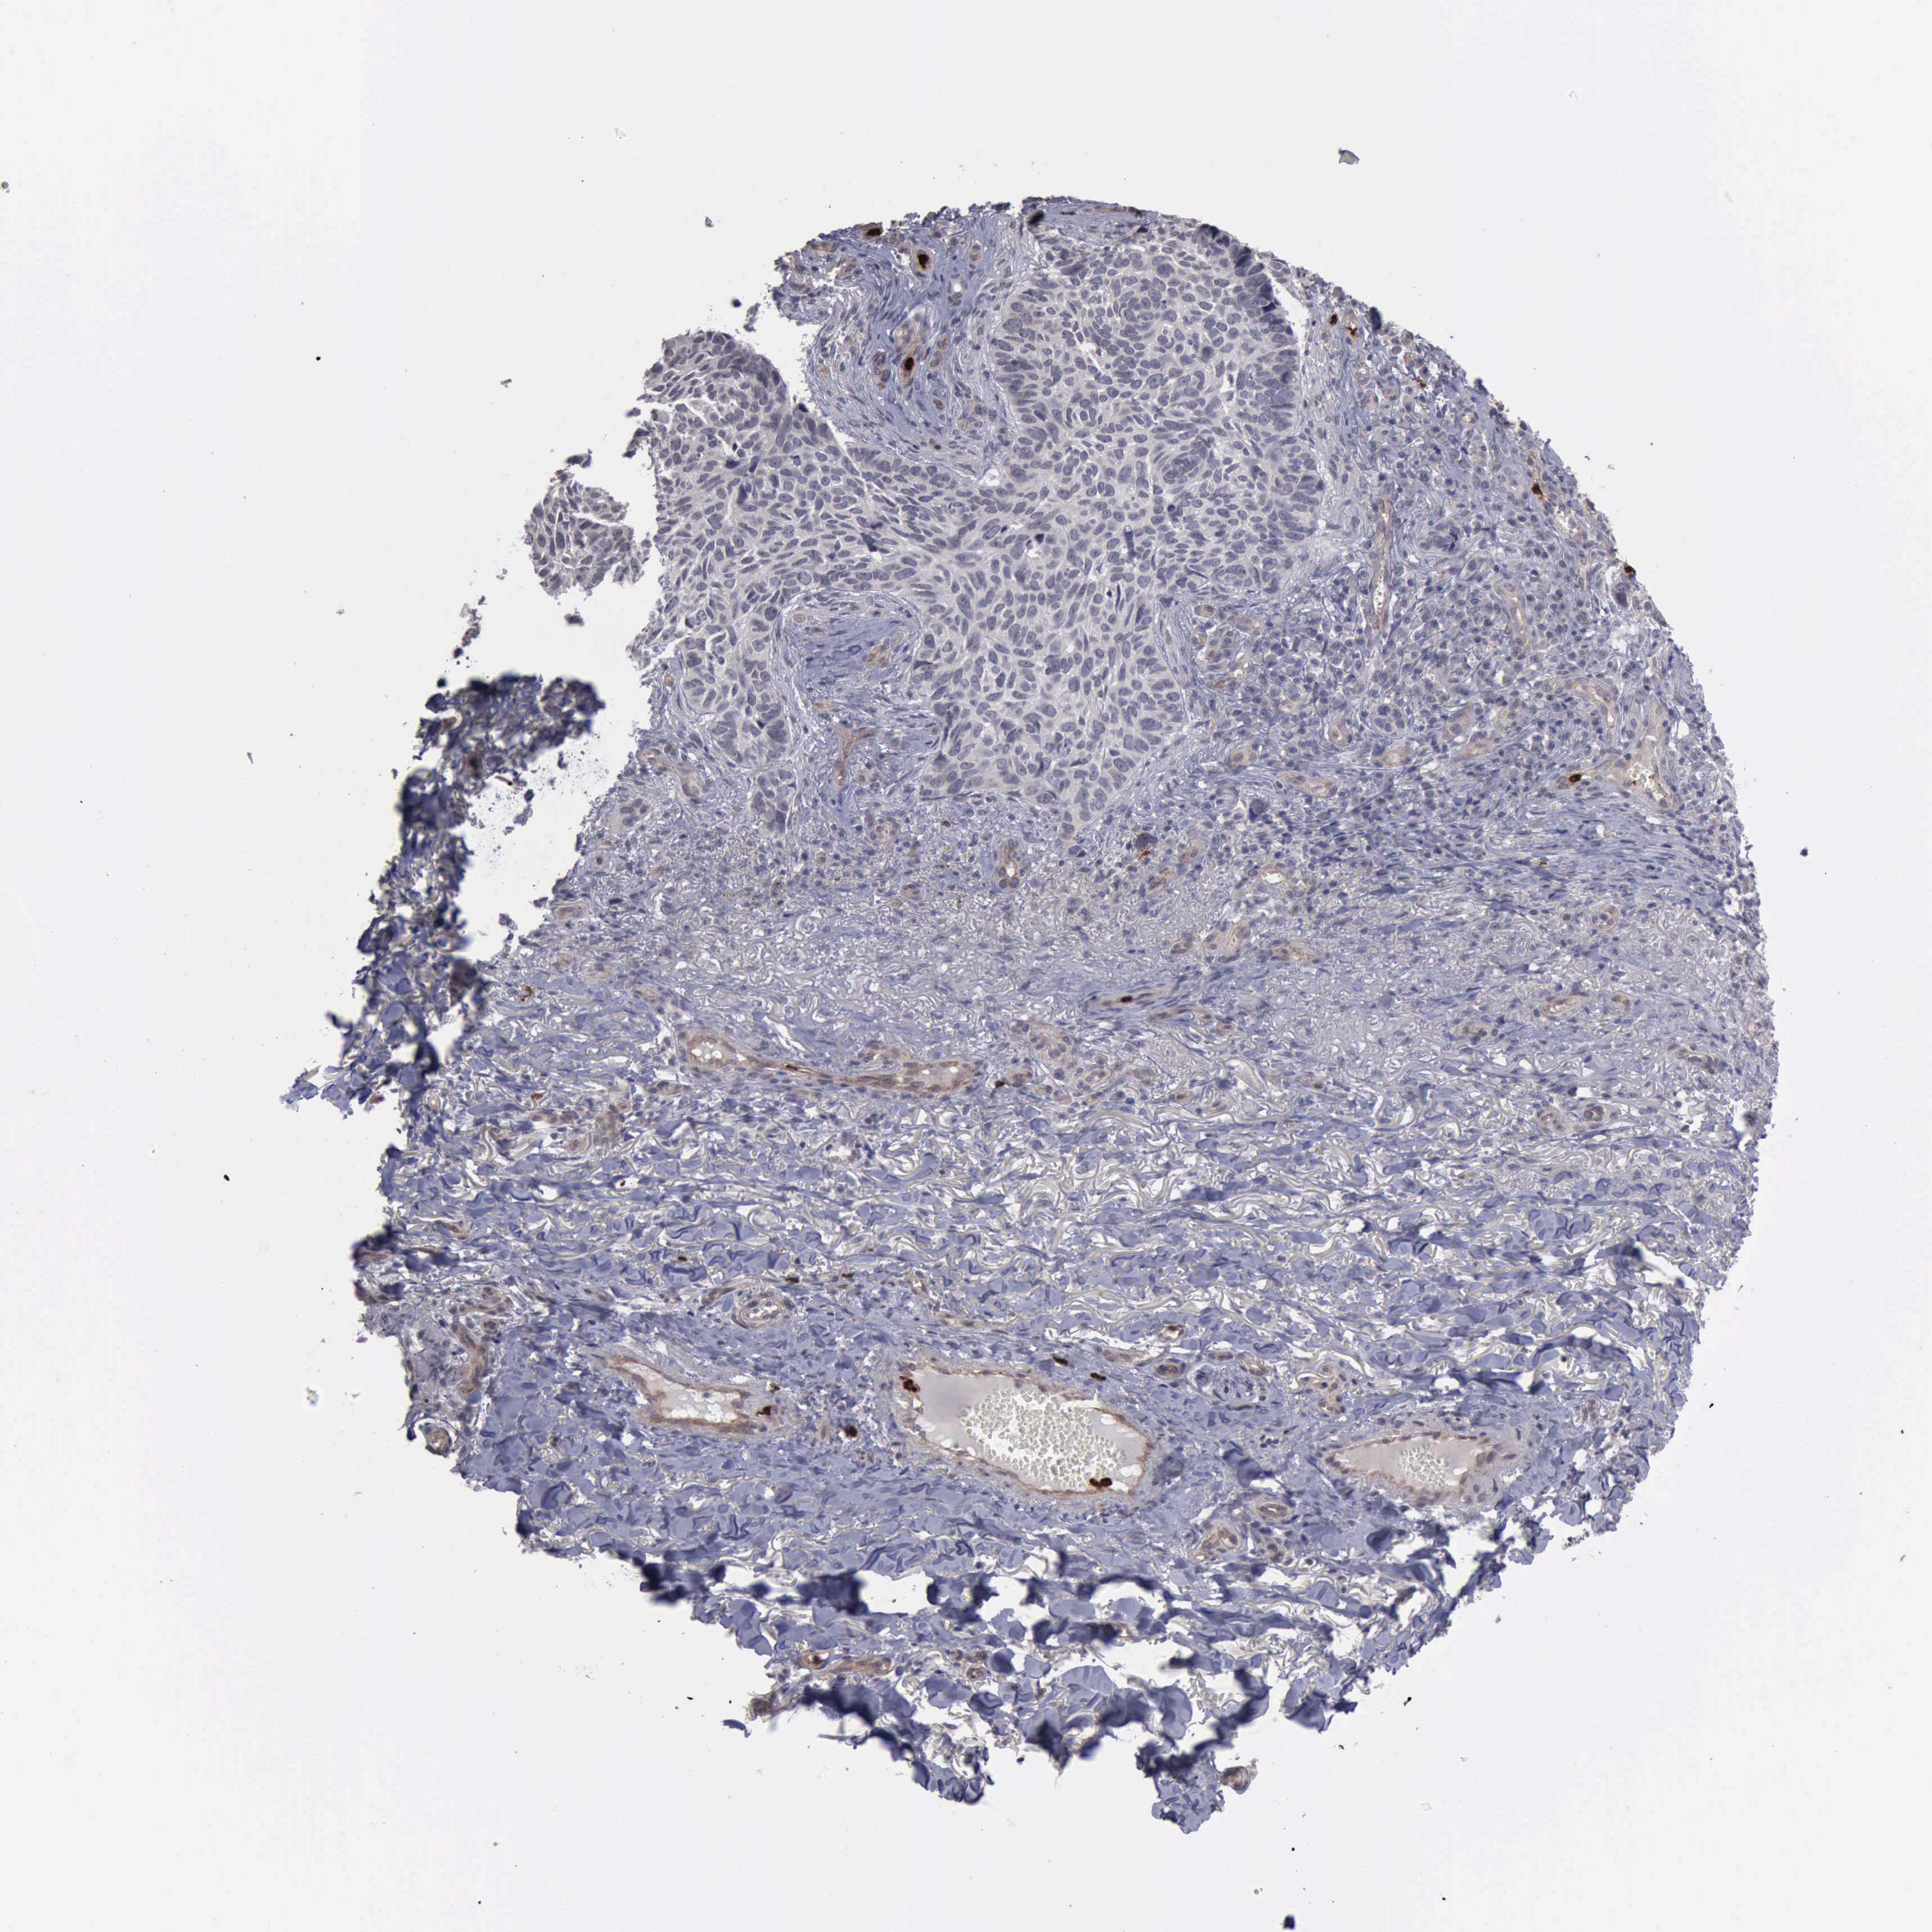

PATHOLOGY SKIN CANCER Show tissue menu

Basal cell and squamous cell cancer

SKIN CANCER - Protein expressioni

A mouse-over function shows sample information and annotation data. Click on an image to view it in a full screen mode. Samples can be filtered based on level of antibody staining by selecting one or several of the following categories: high, medium, low and not detected. The assay and annotation is described here.

Antibody stainingi

Antibody staining in the annotated cell types in the current human tissue is reported as not detected, low, medium, or high, based on conventional immunohistochemistry profiling in selected tissues. This score is based on the combination of the staining intensity and fraction of stained cells.

Each image is clickable and will lead to virtual microscopy that enables deeper exploration of all samples and also displays staining intensity scores, fraction scores and subcellular localization as well as patient and tissue information for each sample.